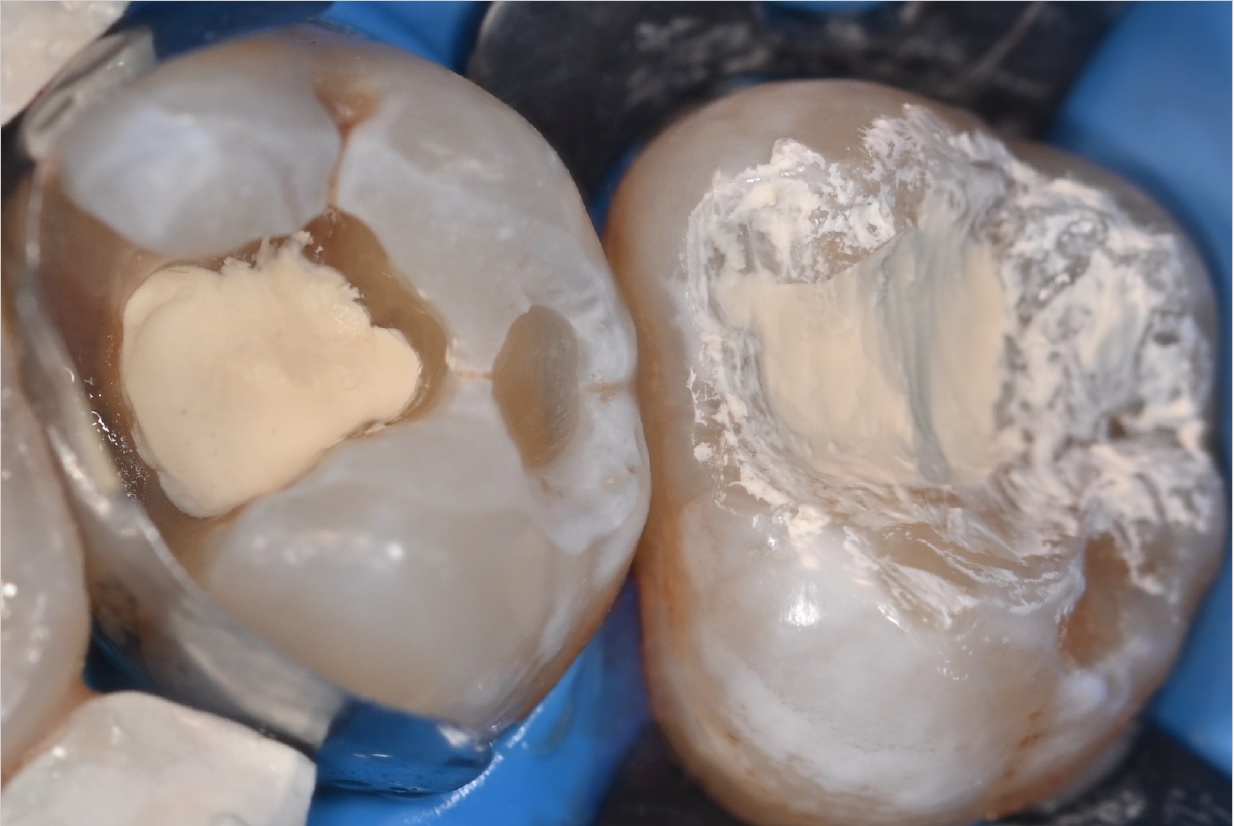

Εικ. 4: Αφού οι κοιλότητες είχαν προετοιμαστεί και καθαριστεί, το Biodentine XP εφαρμόστηκε απευθείας στην βαθύτερη περιοχή της κοιλότητας.

Εικ. 5: Μια κοιλότητα Ομάδος Ι είναι πιο επιθετική στην αφαίρεση όλου του κατεστραμμένου ιστού σε σύγκριση με μια κοιλότητα Ομάδος II και μπορεί να προκαλέσει μεγαλύτερη ευαισθησία. Για να αξιολογηθεί η διατήρηση της ζωτικότητας του πολφού στον τρίτο γομφίο, ο οποίος ήταν ο πιο επηρεασμένος, εφαρμόστηκε το Biodentine XP χρησιμοποιώντας μια τεχνική biobulk-fill, γεμίζοντας πλήρως την κοιλότητα μέχρι την μασητική επιφάνεια ως προσωρινή αποκατάσταση. Αυτή η προσέγγιση επιτρέπει την αναβολή της οριστικής αποκατάστασης, διασφαλίζοντας παράλληλα την σωστή έμφραξη της κοιλότητας για την αποφυγή επιμόλυνσης. Επιπλέον, επιτρέπει την αξιολόγηση της διατήρησης της ζωτικότητας του πολφού και καθορίζει αν απαιτείται ενδοδοντική θεραπεία αν τελικά δεν διατηρηθεί η ζωτικότητα.

Αντίθετα, για τον δεύτερο γομφίο, η ολοκλήρωση της αποκατάστασης Ομάδος II ήταν προτεραιότητα. Έτσι, τοποθετήθηκε το Biodentine XP, αφέθηκε να πήξει και στη συνέχεια καλύφθηκε με σύνθετη ρητίνη για να επιτευχθεί η τελική αποκατάσταση.